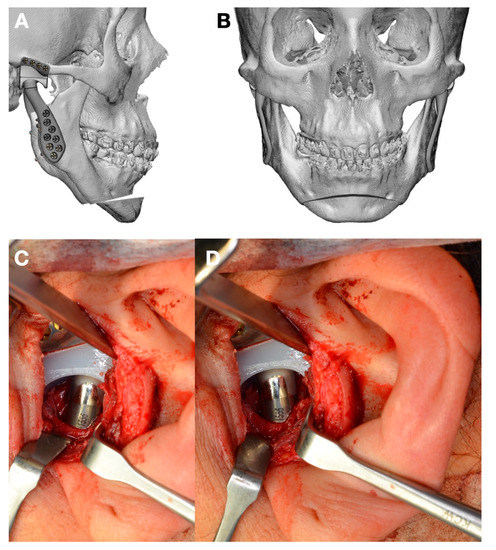

1.3. Clinical Conditions Related to Use of TMJ Replacement

- Malformations, Pathology, or Trauma of the Mandibular Condyle

- Surgical specification for the operation; complementary surgery;